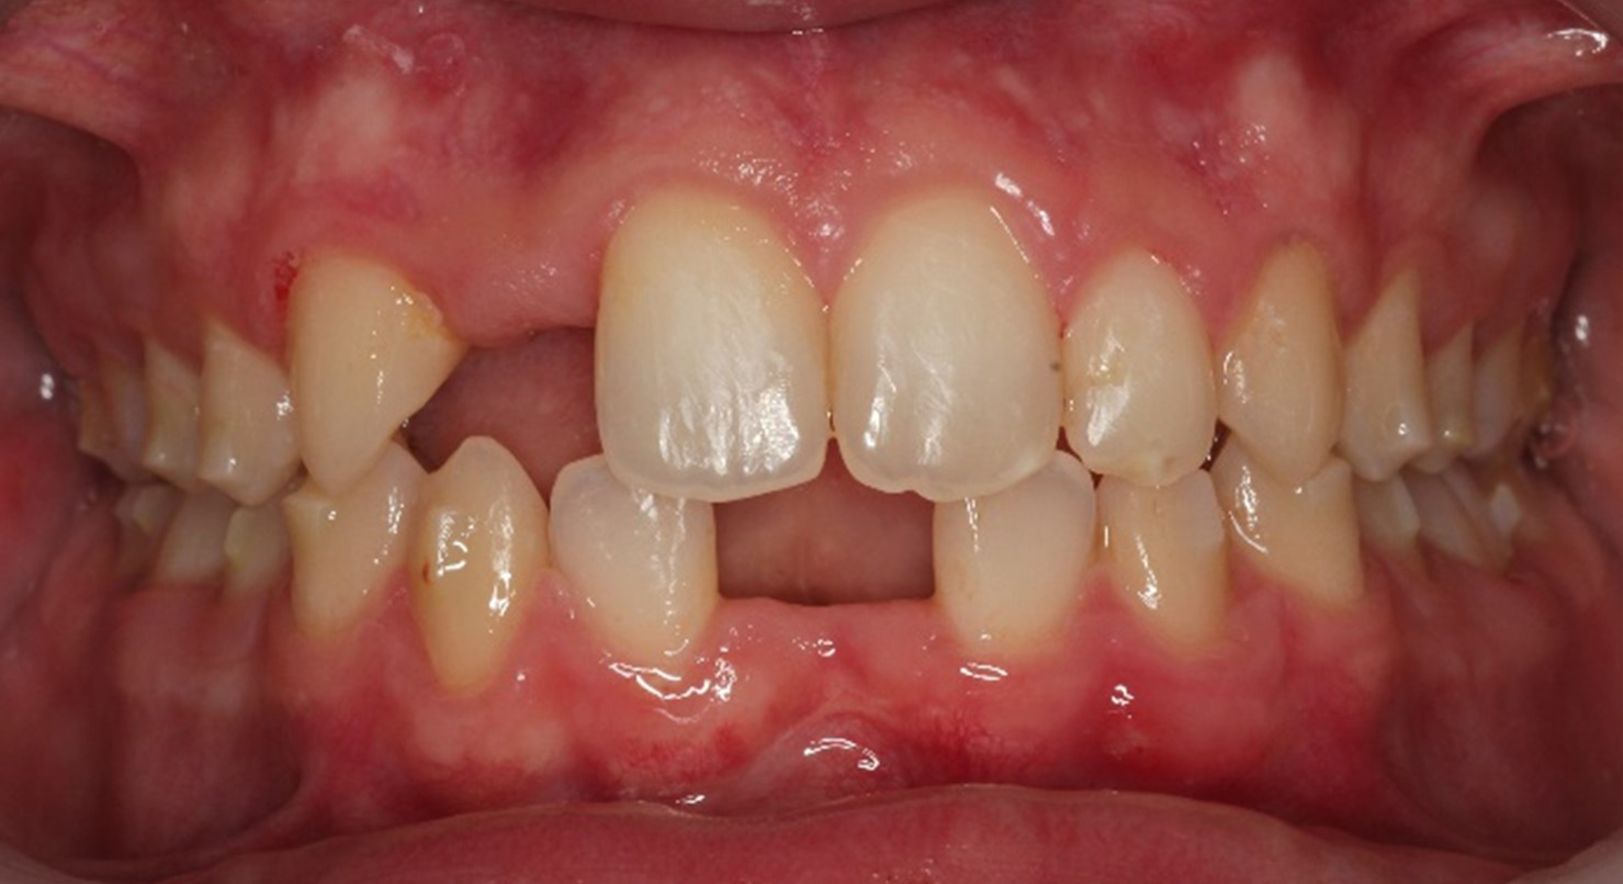

Skeletal Class II due to mandibular retrognathia, proclination of maxillary incisors, narrow arch creating a V-shaped arch, agenesis of 12, 31, 41, hyperdivergent facial pattern, moderate deep bite (2 mm), increased overjet (9 mm), asymmetric canine and molar Class II due to mandibular deviation to the left, maxillary midline deviation related to agenesis of 12, distal rotation of 35 and 45, and pronounced lower curve of Spee.

Upper arch: 20 active aligners

Transverse expansion

Derotation with mesial-out of first molars

Space opening for 12 by distalizing 13

Maxillary midline correction

Lower arch: 31 active aligners

Incisor intrusion using frog staging

Vertical attachments on lower incisors for improved tipping control

Space opening for 31 and 41